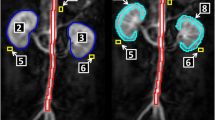

Twenty-four background-corrected renogram TACs using 99mTc-labelled mercapto-acetyl-triglycine (MAG3) with a unilateral obstructive pattern and six normal control renograms TACs were studied. Optimised computed models of each curve were constructed using specialised software (ModelMaker, Cherwell Scientific) and using the Marquardt Least Squares method. Following optimisation to the TAC of each target renogram, the afferent flow rate parameters were calculated.

Following optimisation of models, afferent flow rate parameters, expressed as arbitrary units, (mean 0.15, SD 0.06) in acutely obstructed kidneys, were typically reduced in comparison with those of normal kidneys (mean 0.44, SD 0.04). (Paired t test; P < 0.005). By contrast, this reduction in afferent flow rate parameter was greater than the reduction in differential tracer uptake for the obstructed kidney (divided renal function of the obstructed group; mean 0.3, SD 0.14 compared with the control group; mean 0.45, SD 0.05 (P < 0.05).